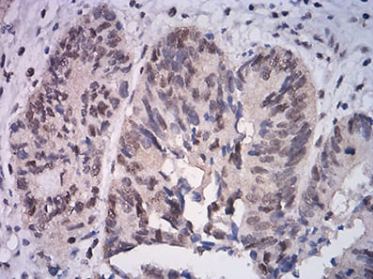

ATF4 Mouse Monoclonal antibody[2A6F1]

IHC    1/200 - 1/1000